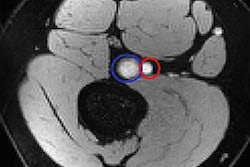

(A-C) Example of pulmonary perfusion images obtained by using noncontrast-enhanced matrix pencil MRI in three different tobacco smokers before exposure (preexposure) and after exposure (postexposure). The images before and after exposure were acquired at corresponding coronal section locations. Arrows indicate lung regions with decreased regional perfusion after the exposure to nicotine. Red corresponds to high values of ventilation amplitude and perfusion amplitude, whereas blue corresponds to low values. Images and caption courtesy of the RSNA.Electronic cigarette (e-cigarette) users demonstrated a reduction in the percentage of lung impairment after exposure (which can impact ventilation) on the second MRI scan. In tobacco smokers, however, there was a decrease in lung perfusion after exposure (which impacts blood flow in the lungs), as indicated by a higher percentage of lung impairment. These were the only results that were statistically significant.